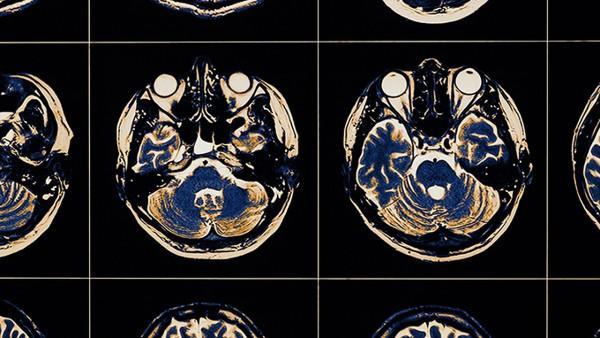

多汗症是一种常见的病症,表现为在没有明显刺激的情况下,局部或全身过度出汗。这种情况不仅会对患者的生活质量造成影响,还可能引发一些心理上的困扰。关于多汗症是否会影响免疫力,这一问题仍然较少被深入探讨。

免疫系统是体内抵御病原微生物、病毒和其他有害物质的重要防线。它由多种细胞、组织和器官协同工作,保持身体的健康状态。在正常情况下,免疫系统会不断地适应外部环境的变化,调节其反应强度。